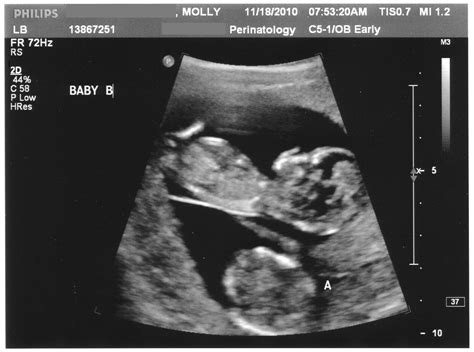

The Nuchal Screening Ultrasound, frequently referred to as the Nuchal Translucency (NT) scan, is a non-invasive diagnostic procedure performed between 11 and 14 weeks of pregnancy. During this examination, a sonographer uses ultrasound technology to measure the clear space in the tissue at the back of the baby’s neck. This area, known as the nuchal translucency, contains a small amount of fluid. While all fetuses have some fluid in this region, a measurement that is larger than average can be an indicator of an increased risk for chromosomal conditions, such as Down syndrome (trisomy 21), Edwards syndrome (trisomy 18), or Patau syndrome (trisomy 13), as well as certain structural heart defects.

The procedure is relatively straightforward and is usually performed by a trained sonographer. You will be asked to lie on an examination table, and a conductive gel will be applied to your abdomen. The sonographer will then move a transducer—a device that emits sound waves—over your belly to capture images of your baby on a monitor. Because the baby is still quite small during the 11 to 14-week window, the sonographer needs precise images to ensure the accuracy of the nuchal measurement.

• Crown-Rump Length (CRL): To accurately determine the gestational age of the fetus.

• Nuchal Translucency Thickness: The core focus of the screening.

• Fetal Anatomy: A preliminary look at the baby's development, including the skull, spine, heart, and limbs.